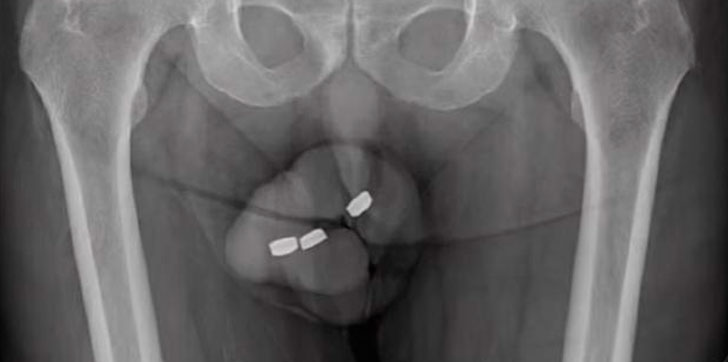

AUSTRALIA- Un australiano perdió parte de su pene al introducirse pilas de rejos de un centímetro en su uretra con el fin de obtener «gratificación sexual», el hombre de 72 dijo que, en el pasado, había podido retirar los objetos sin problema.

Según el informe médico, este hombre intentó retirar las baterías con sus propias manos, pero esta acción solo causó que se introdujeran más en su miembro.

Luego del primer exámen, el hombre fue remitido para una cirugía, pues los médicos sospechaban que podría tener un daño más profundo y fue sometido a anestesia general para poder retirar las batería sin que sintiera dolor.

En medio de la intervención, los médicos también descubrieron que el australiano habría sufrido una necrosis y que parte de su prepucio había quedado atrapado por las baterías al interior de su pene.